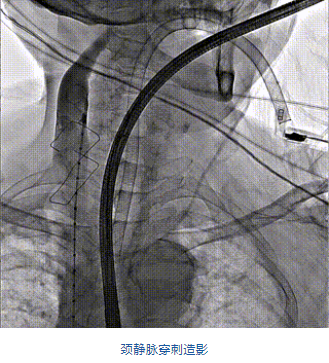

團(tuán)隊前期經(jīng)過多次討論,制定了周密的手術(shù)策略和預(yù)案。由于患者已是近九旬的超高齡老人,傳統(tǒng)外科開胸手術(shù)風(fēng)險極高,純介入經(jīng)血管三尖瓣替換能夠明顯減少創(chuàng)傷。術(shù)中陳茂及馮沅教授結(jié)合體表定位在造影指示下精準(zhǔn)穿刺右側(cè)頸靜脈并預(yù)置兩把血管縫合器。成功建立經(jīng)皮血管入路后在食道超聲和DSA的引導(dǎo)下順利完成人工瓣膜植入,術(shù)后超聲和造影顯示人工三尖瓣同軸性良好,瓣架固定牢靠,無反流和瓣周漏,平均跨瓣壓差降為1mmHg。術(shù)畢收緊預(yù)置的血管縫合器縫線完成止血,縫合效果滿意,在手術(shù)室即刻拔除氣管插管。